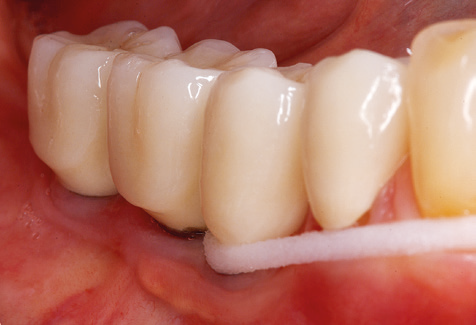

Nach der maschinellen Reinigung der Zahn und Implantatoberflächen erfolgt eine manuelle Instrumentierung der natürlichen Zahnoberflächen mit konventionellen Handinstrumenten. Bei der manuellen Reinigung ist insbesondere auf einen korrekten Anstellwinkel, eine ausreichende Schärfe, eine gute Abstützung und auf eine von apikal nach koronal gerichtete Arbeitsweise der Kürette zu achten. Zur Nachinstrumentierung der Implantatkonstruktionen sollten entweder Titan oder Carbonküretten verwendet werden (Abb. 8). Ergänzend zum Einsatz von Ultraschallgeräten können in der Erhaltungstherapie auch Pulverstrahlgeräte genutzt werden. Dabei ist jedoch zu berücksichtigen, dass diese Verfahren nicht zum Entfernen harter Beläge geeignet sind und daher die Verwendung von Hand oder Ultraschallinstrumenten nicht komplett ersetzen können. Abschließend erfolgt in jedem Fall eine mechanische Politur der zugänglichen Zahn und Implantatoberflächen mit Polierkelchen und Polierpasten (Abb. 9).

Für den klinischen Langzeiterfolg des parodontal kompromittierten Patienten ist die standardisierte und regelmäßige risikoadaptierte Betreuung im Rahmen der UPT der zentrale Baustein des Behandlungserfolgs. Dies gilt in besonderer Weise für Patienten, die nach erfolgreich abgeschlossener parodontaler Sanierung mit Implantaten versorgt wurden (Abb. 11a und b).